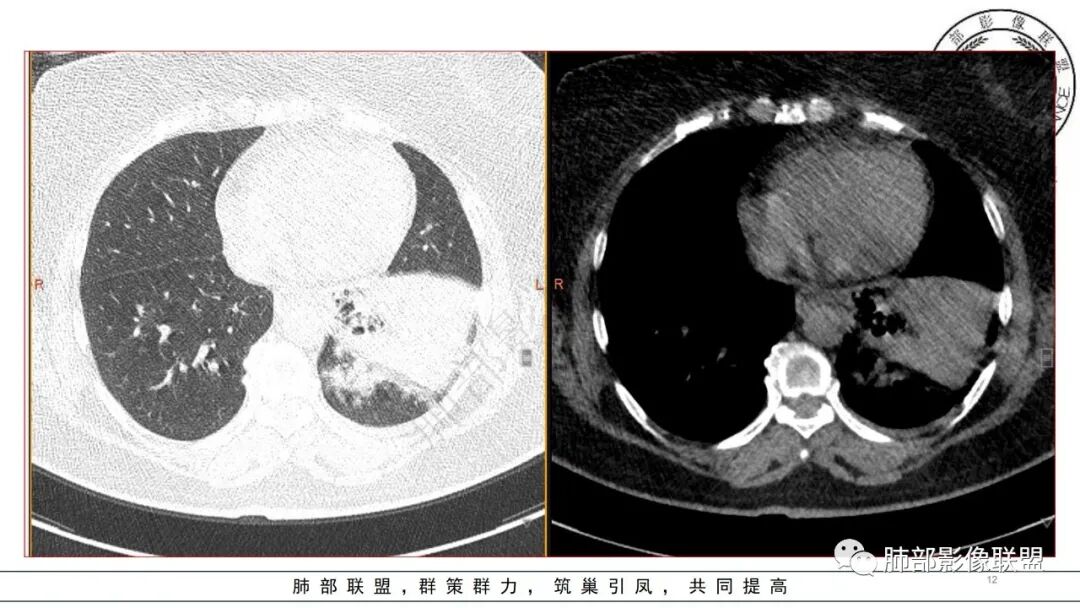

3.五天后及十三天后病灶变化明显,实性密度影吸收缩小,边界趋于清楚,显示多空腔。

1.局限于单肺叶的大范围实性密度影,边界不清,看不出外壁的液化空洞,多符合化脓性感染。

2.数天内变化明显,肿瘤性病变,结核、真菌、努卡等感染几乎不在鉴别诊断之列。

4.肺炎克雷伯杆菌肺炎病灶也易形成脓腔。本例患者未出现典型金葡感染影像学特征,患者临床表现相对“逍遥”缓慢,结合实验室检查,更符合肺炎克雷伯杆菌肺炎。